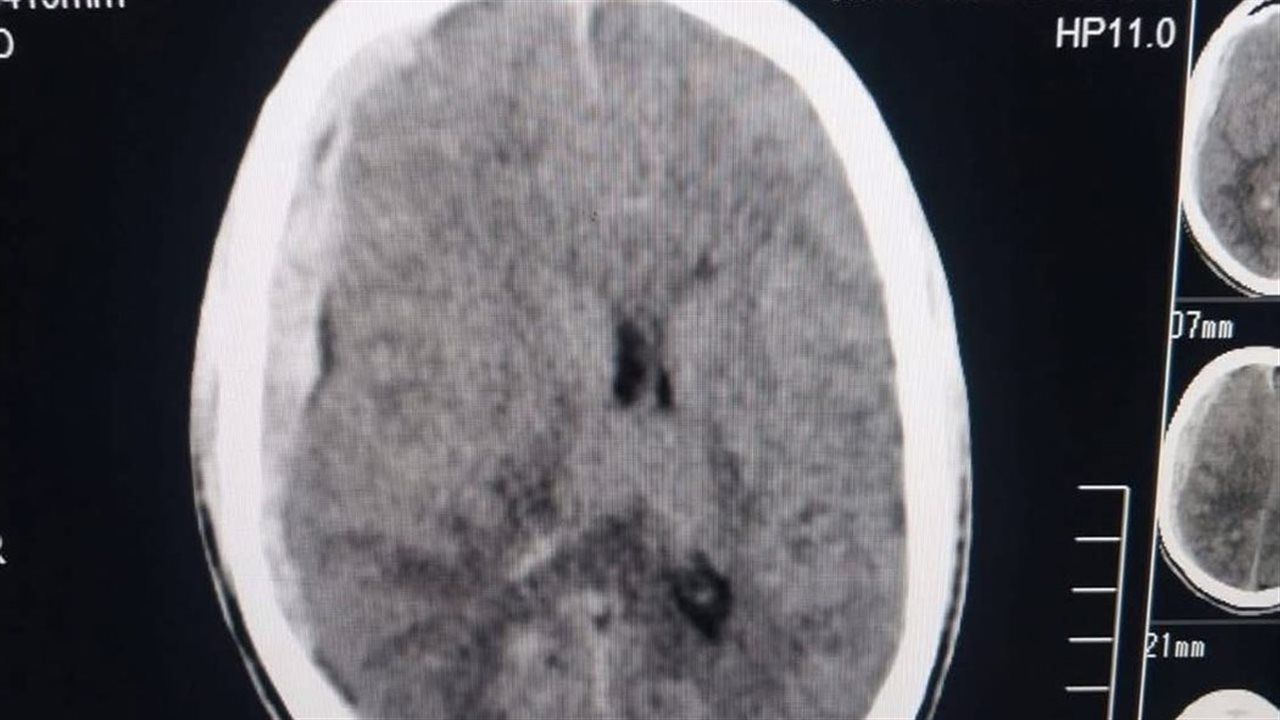

وتم التعامل مع الحالة بشكل فوري وفق بروتوكولات الطوارئ المتقدمة، حيث جرى تأمين مجرى الهواء عن طريق تركيب أنبوبة حنجرية، ووضع المريض على جهاز التنفس الصناعي. كما أظهرت الأشعة المقطعية على المخ وجود نزيف تحت الجافية (SDH) ونزيف تحت العنكبوتية (SAH).

وتم حجز المريض بوحدة عناية الطوارئ والحالات الحرجة المركزة، حيث خضع للعلاج التحفظي مع متابعة دقيقة لمستوى الوعي والعلامات العصبية. وأكدت إعادة الأشعة المقطعية استقرار الحالة وعدم زيادة حجم النزيف، مما دعم الاستمرار في الخطة العلاجية.

وبفضل المتابعة الدقيقة والرعاية المتكاملة، تحسنت الحالة بشكل ملحوظ حتى وصلت إلى درجة الوعي: 15/15 معدل التنفس: 18/دقيقة ونسبة الأكسجين: 99% على هواء الغرفة، كما أظهرت الأشعة تحسنًا واضحًا وانخفاضًا في حجم النزيف.